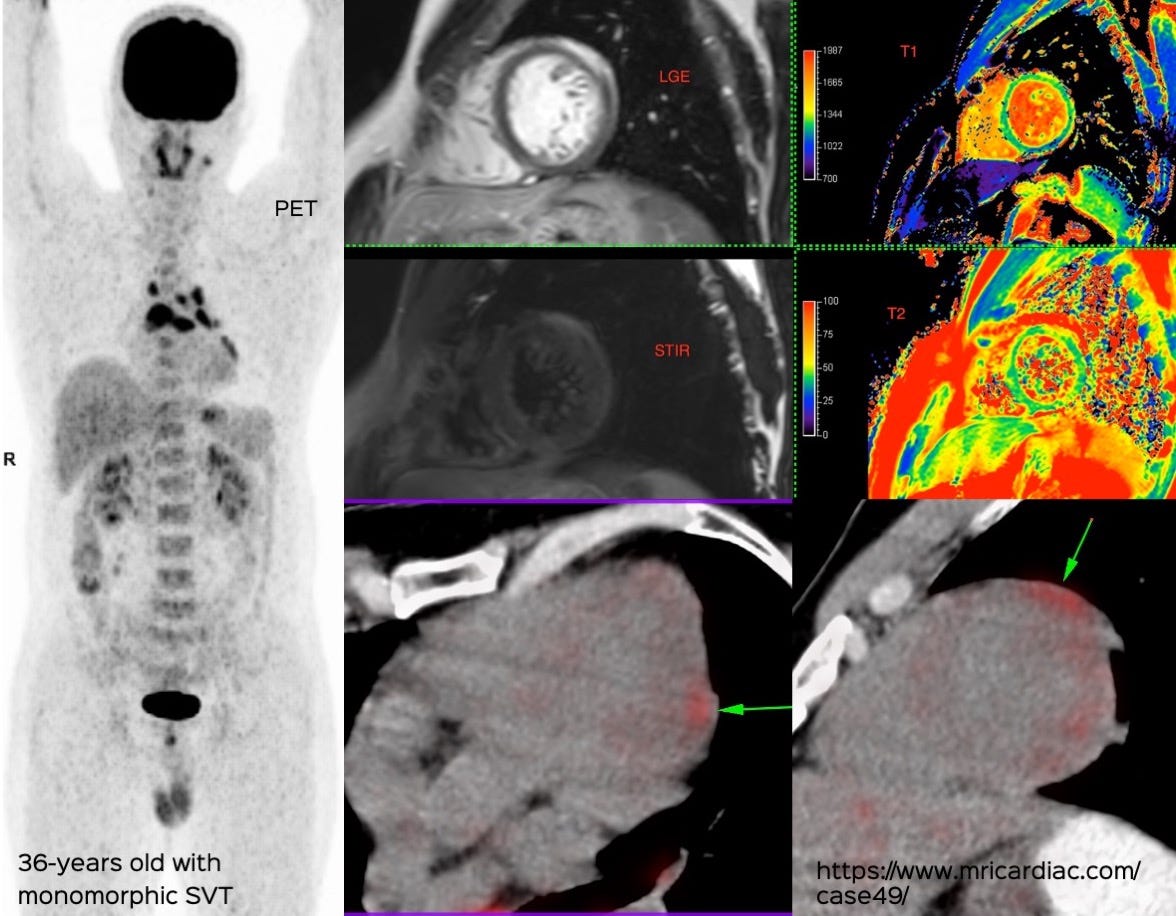

A 39-years old was found to have a mass in the chest on a CT chest done for COVID-19.

What is the likely diagnosis?

Paraganglioma